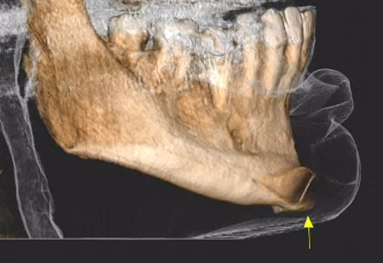

Εκτός από τις παραπάνω ελάχιστα επεμβατικές τεχνικές, στις απεικονίσεις της τραχηλοπροσωπικής χώρας μπορεί να συναντήσουμε και τα αποτελέσματα πιο επεμβατικών τεχνικών, όπως διάφορες μορφές πλαστικής χειρουργικής με χρήση ενθεμάτων σιλικόνης.

Ένα παράδειγμα είναι η γενειοπλαστική, όπως φαίνεται στην παρακάτω περίπτωση.